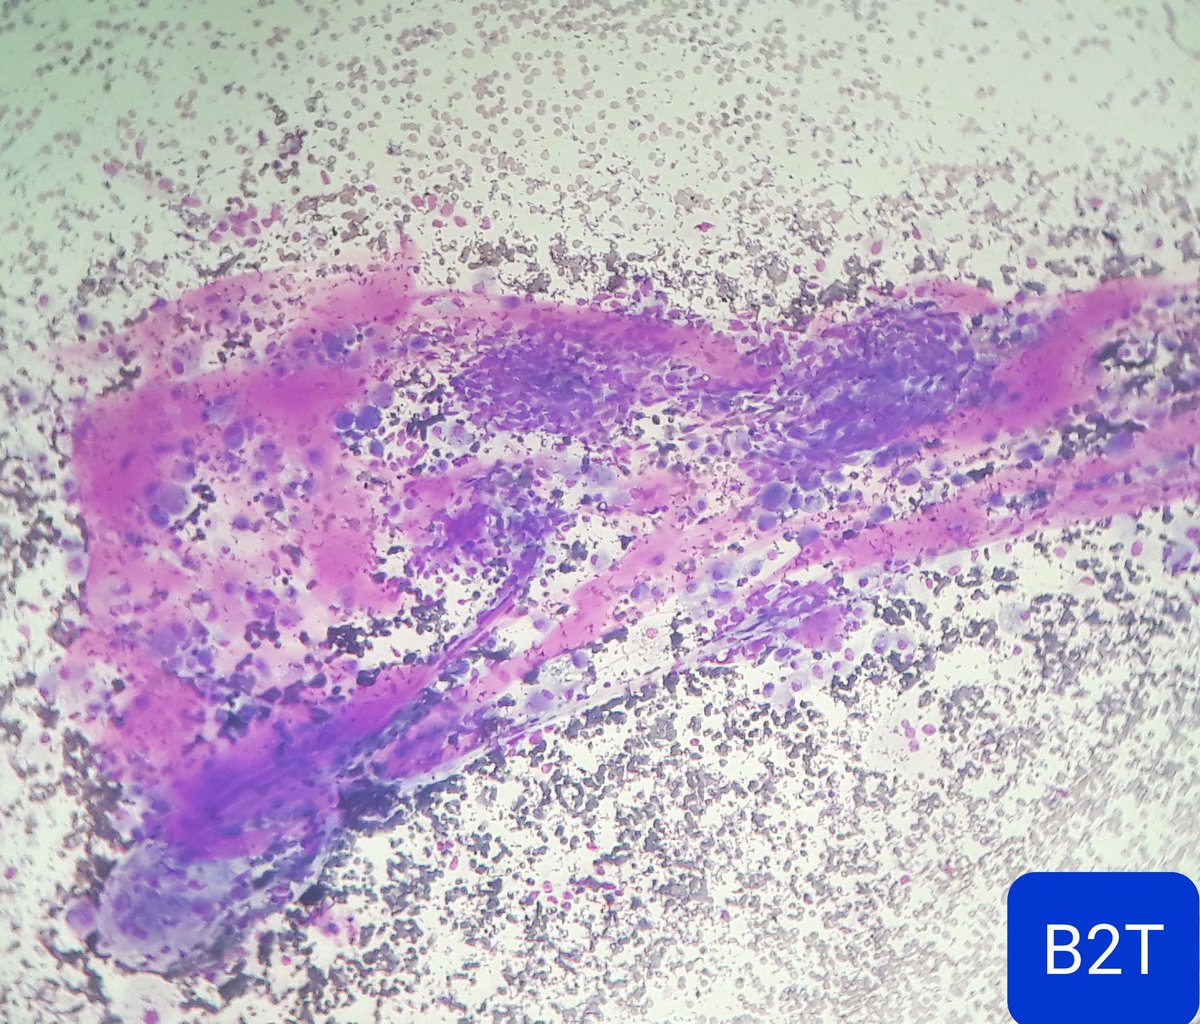

"Two-in-one": lung AC in a pleural effusion: the same cells stained with papanicolaou and then with TTF1. "Cytopathology, doing more with less...."🔬✌️🎯💯🔝 Sociedad Española de Citología SEAP-IAP Cytopathology.org International Academy Cytology